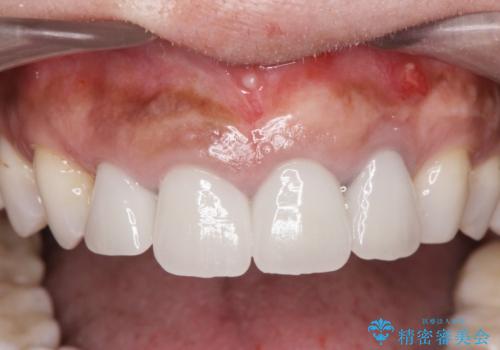

- 前歯がグラグラし、においもする、とのことで改善を求めて来院されました。

一見して問題ないように見える左側の2前歯は、セラミックを除去してみると亀裂や虫歯の再発が見られました。

抜歯時に可及的に歯肉のボリュームを保つよう骨充填材とコラーゲン製剤による填塞を行い審美的かつ機能的なブリッジとなるよう治療を進めます。